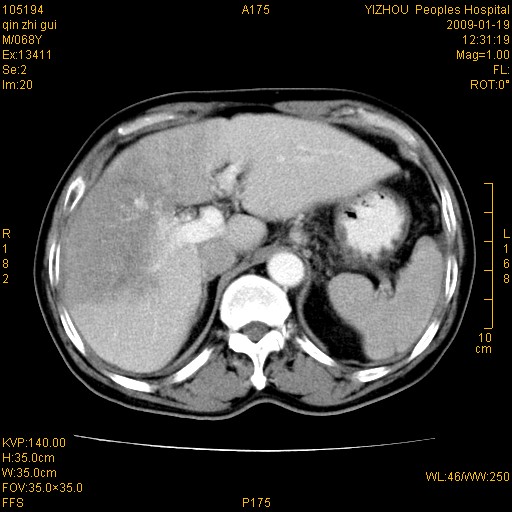

以下是引用随光逐影在2009-1-21 16:11:00的发言:[br]1)考虑肝右叶肝癌并肝静脉及门静脉瘤栓形成。2)肝硬化,少量腹水。3)胆囊炎。4)右侧少量胸腔积液。

病灶外缘凹凸不平,平扫低密度,增强动脉期有强化,门脉早显,静脉期及延期呈延迟强化,结合病史考虑右肝前叶巨块型肝癌可能性大,强化表现不除外胆管细胞癌